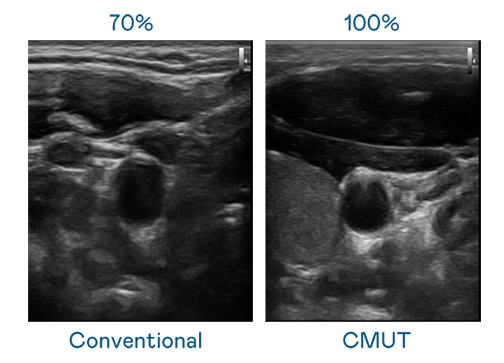

CMUT 技术是一种用电容式微机电元件来产生超音波讯号的技术。与传统 PZT 压电式技术相比,CMUT 频宽增加 30%,更宽频的超音波讯号让影像解析度大幅提升,是实现高影像品质医疗超音波扫描、促进精准医疗发展的关键技术。

大频宽带来超清晰影像

超音波影像的解析度高低,首先取决于探头能发出的讯号频宽。德扑之星 CMUT 可提供高清晰的超音波讯号,提供高频宽、高灵敏度、影像纹理细节更高的超音波影像,协助医护人员缩短影像判读时间及利用精准的医疗影像进行诊断。